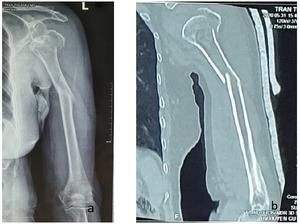

A 79-year-old female was referred to our emergency department with a painful left arm shortly after slipping on a wet floor. Initial assessment revealed no life-threatening injuries, severe pain and swelling from her shoulder to the middle third humerus, angular deformity in the middle third, bony crepitus palpable in the injured site, and no neurovascular impairment. X-ray delineated that a three-part humeral head fracture involved greater tuberosity and surgical neck fragments, anterior glenohumeral dislocation, and spiral fracture of the humeral shaft. A shoulder CT scan was indicated to obtain further information for operative planning, demonstrating a three-part fracture with little bone loss; and a calcar fragment > 8mm and its displacement < 2mm (Fig 1).

The vascular supply of the proximal humerus originated from the anterior circumflex humeral artery and posterior circumflex humeral artery. Hertel et al. measured humeral blood supply by Doppler laser and discovered that if the calcar fragment of humeral head fracture is measured over 8mm and displaced below 2mm, the risk of avascular necrosis of humeral head is significantly low due to no impairment of its blood supply.6 In our case, the imaging findings (CT scan and X-ray) showed the calcar fragment with measurement above 8mm and minimal displacement, thereby reflecting a low risk of avascular necrosis. As a result, osteosynthesis is considered as a reasonable option for this case.